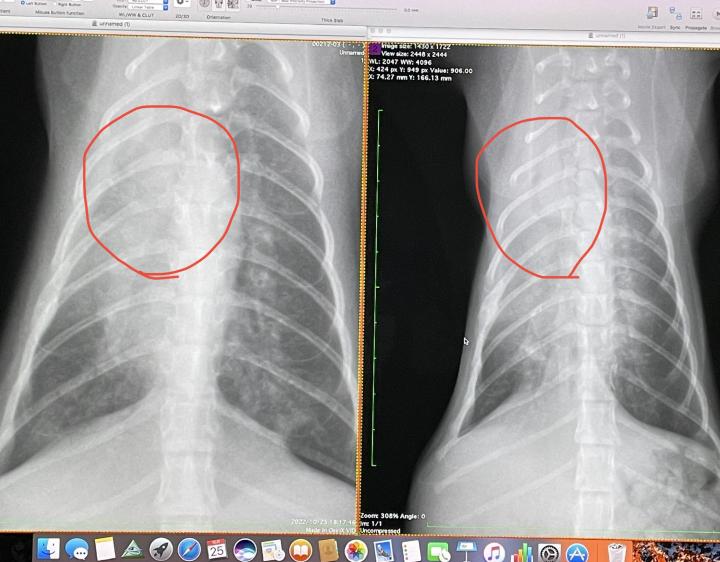

右退院時

左火曜日

赤マルの左肺へ伸びる管がボヤけている

=周辺の肺胞組織が機能し始めた

ということだそうです

つまり

回復傾向である‼️